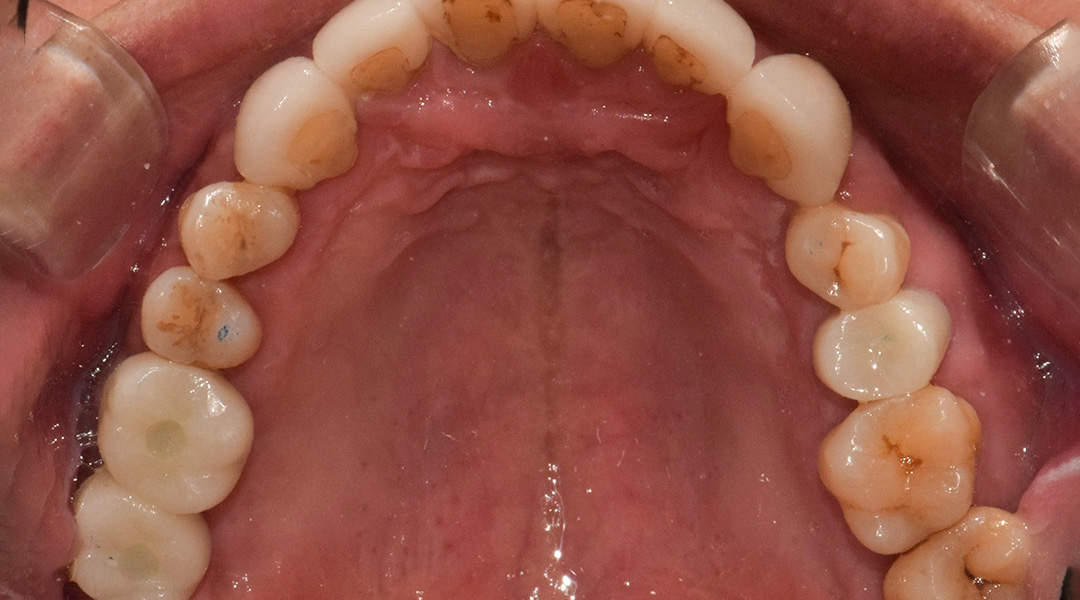

BEFORE & AFTER

갤러리치과의원의 전후 사진을 확인해보세요.

- 충치 / 일반치료

- 화이트레이어